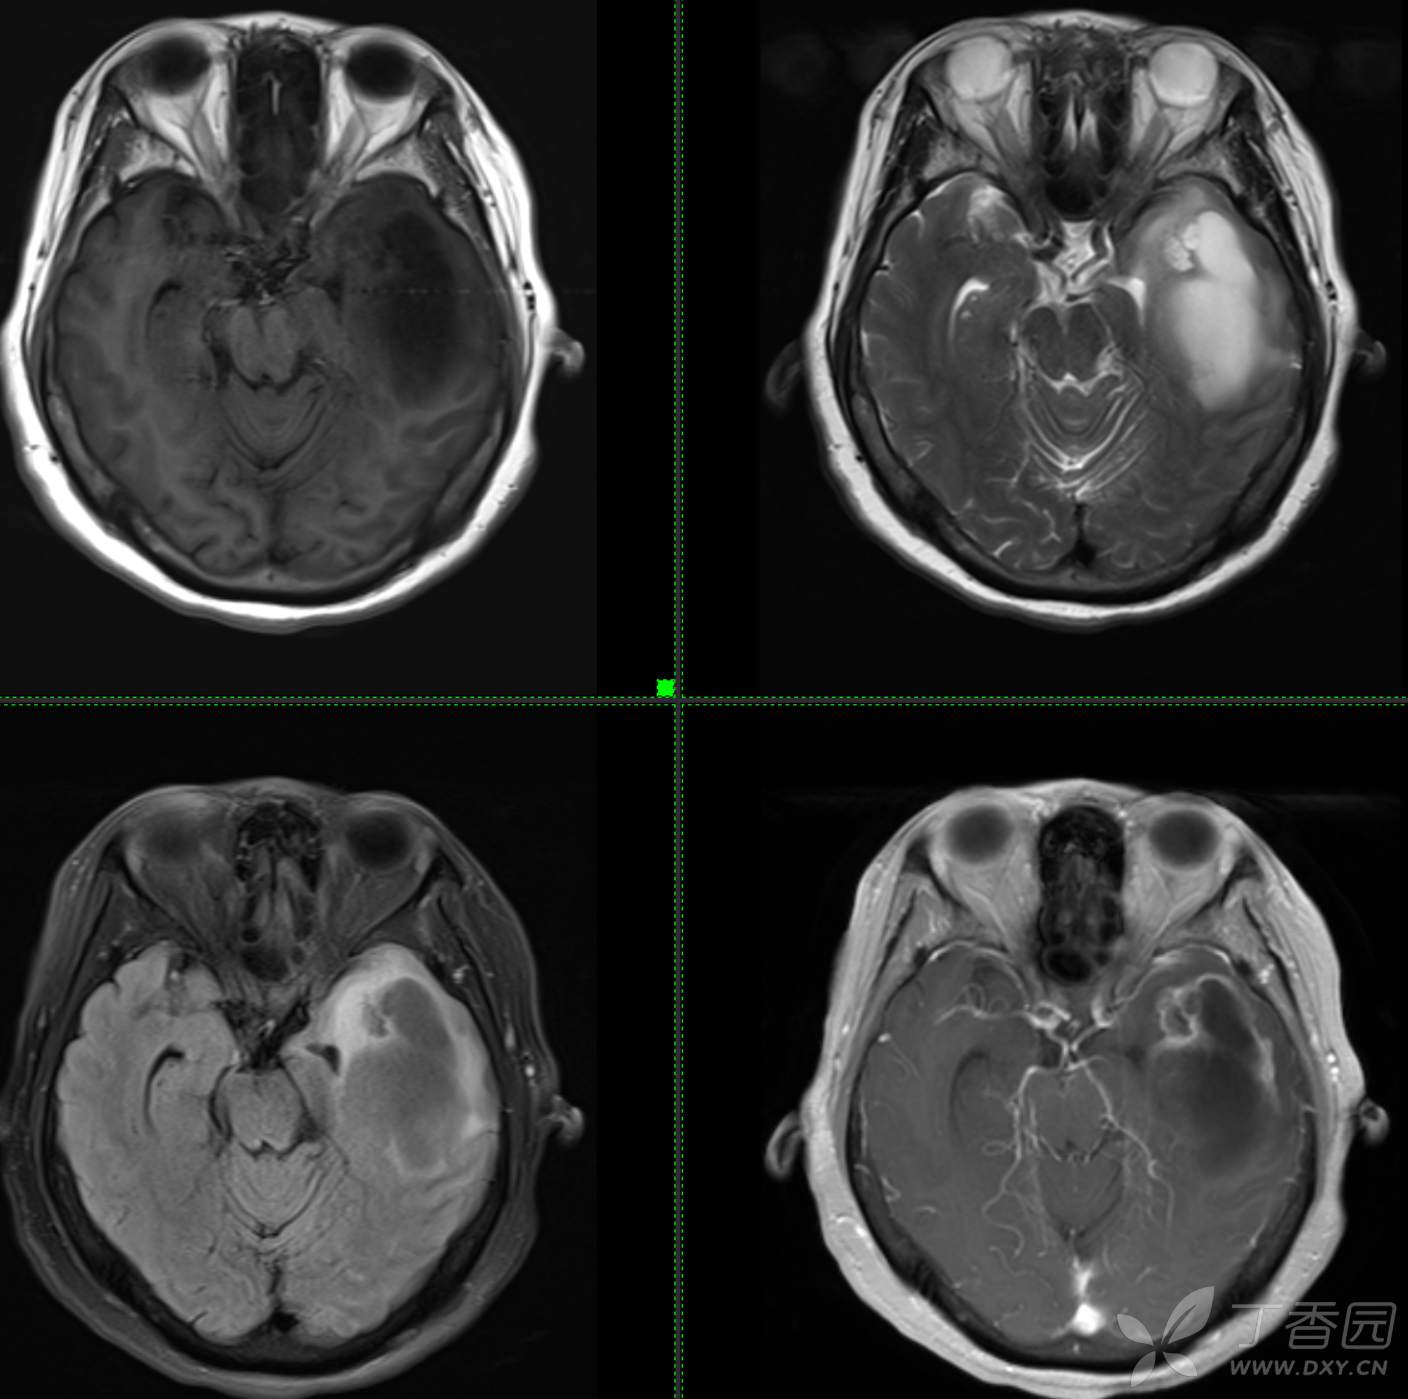

头颈组12:老年女性,原发?继发?

患者年龄:58岁

现病史: 【患者1月余前无明显诱因出现记忆力减退,易忘记事情,表现为忘记说过的话、易忘 事、理解力及计算力均尚可、阅读无受限、无性格脾气改变,无头痛头晕、无恶心呕吐、无视物模糊,无言语不利,无幻觉妄想,当时未重视未就诊。1月内记忆力减退进行性加重,对刚做过的事情即遗忘,计算力下降,日常生活尚能自理。遂至我院门诊就诊,查“颅脑CT平扫:左侧基底节-颞叶区低密度占位,建议进一步增强 MRI检查。

患者既往子宫内膜癌手术史;高血压病史3年